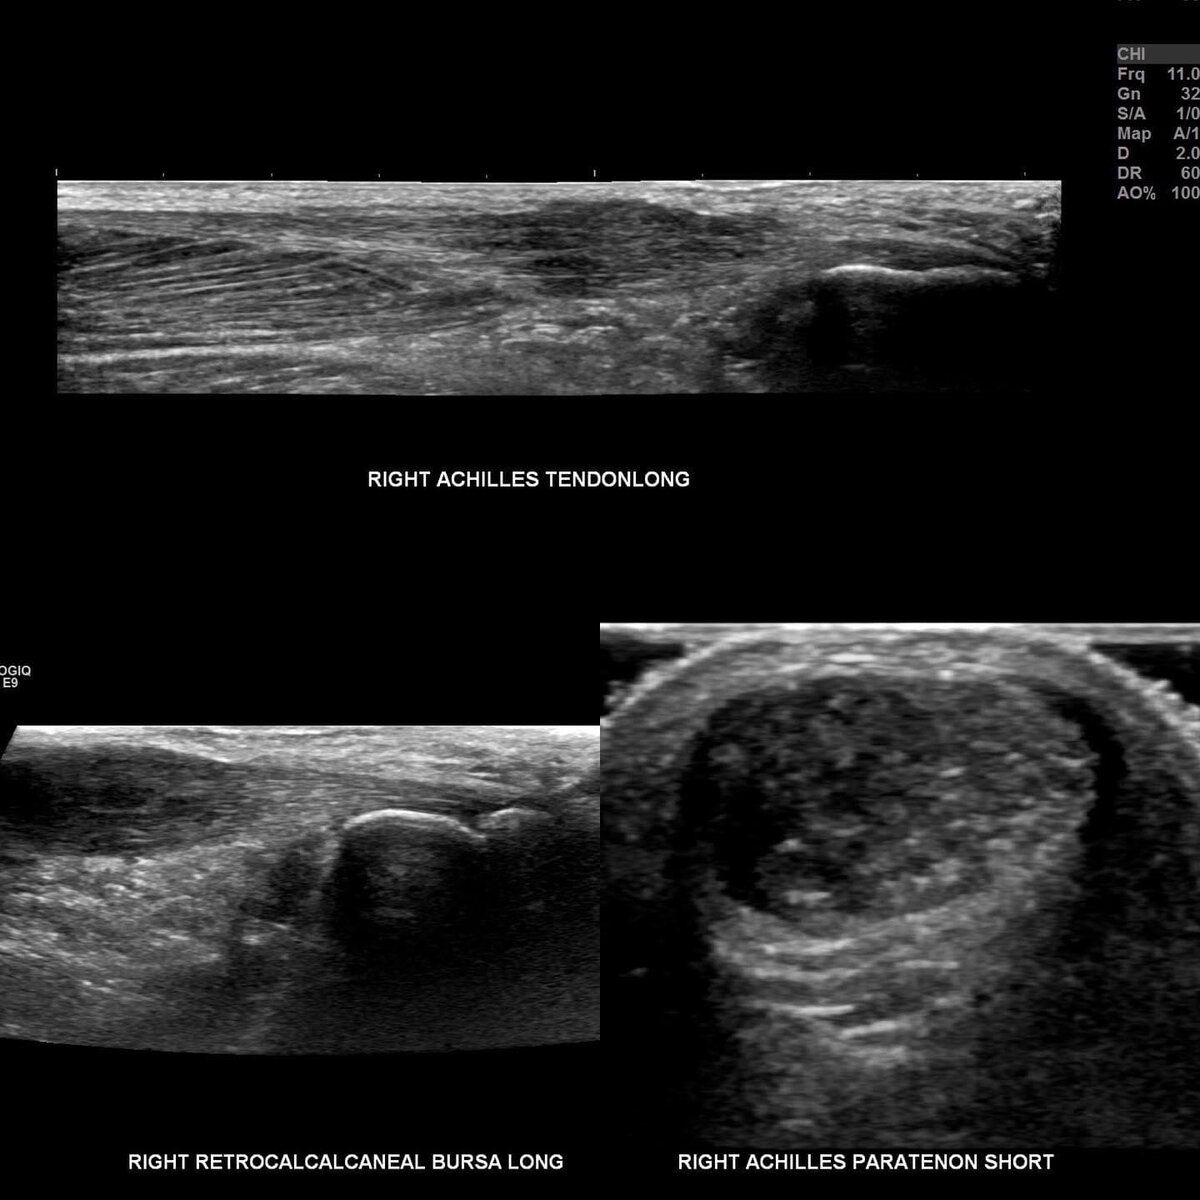

Diagnosing tendonitis typically involves a physical examination and a review of your medical history. Your healthcare provider may ask about your symptoms, the activities that aggravate the pain, and any recent injuries. Imaging tests, such as X-rays, ultrasound, or MRI, may be ordered to rule out other conditions and confirm the diagnosis.

Diagnosing tendinosis involves a physical examination and a review of your medical history. Your healthcare provider may ask about your symptoms, the activities that aggravate the pain, and any recent injuries. Imaging tests, such as ultrasound or MRI, can help confirm the diagnosis by revealing degenerative changes in the tendon.